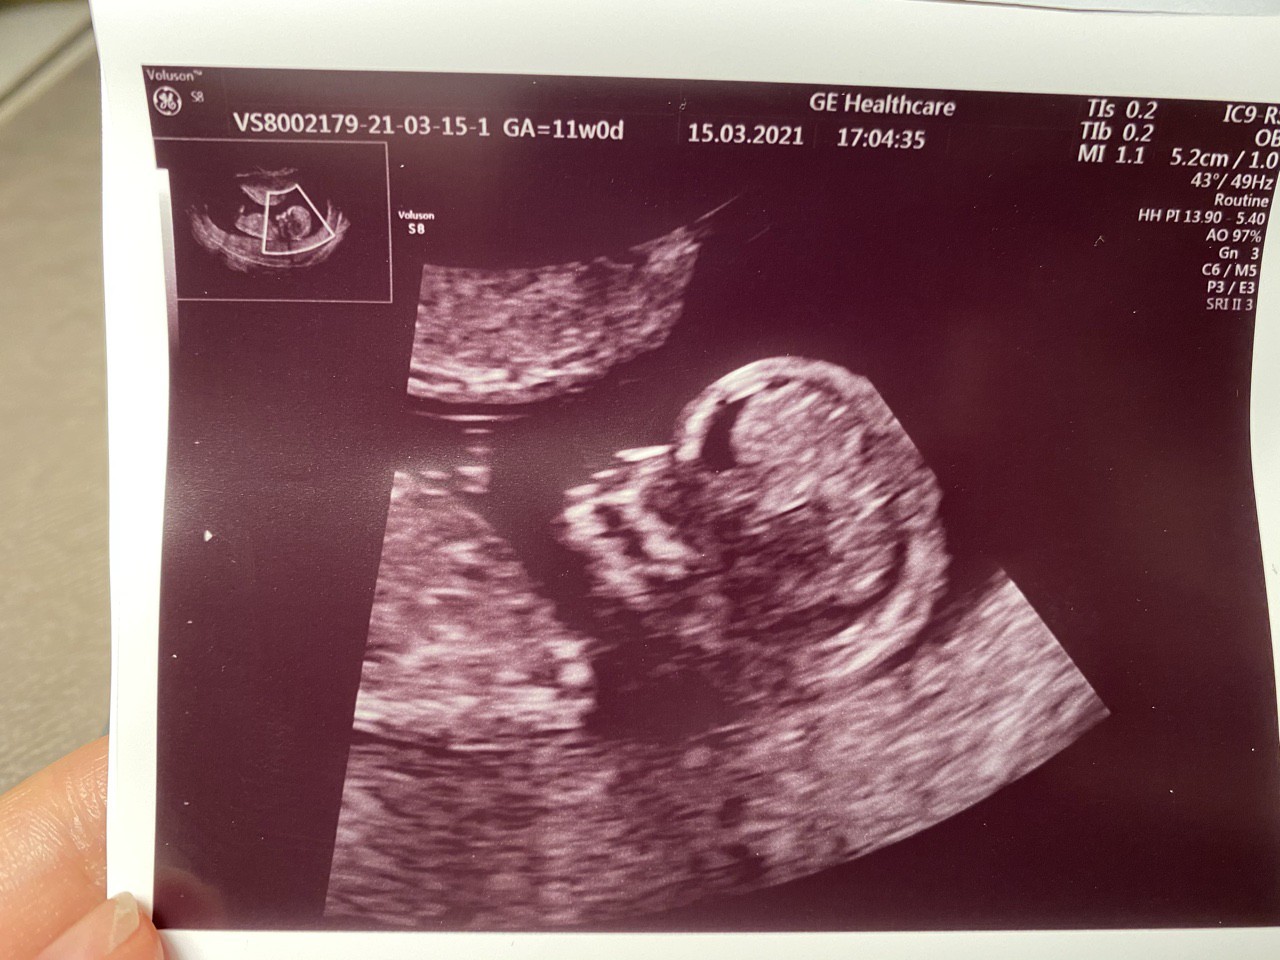

11+0 ❤️

CRL 4cm

FHR 163